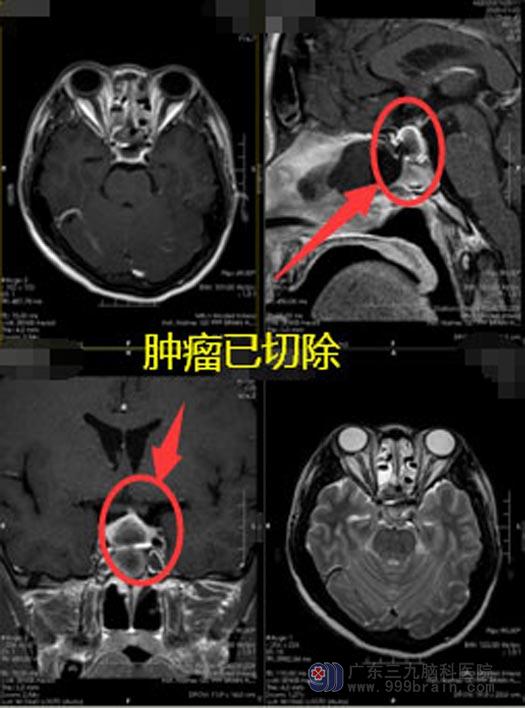

▲手术后

经过一段时间治疗,陈姐病情稳定,内分泌检验结果提示生长激素降至正常范围内,自诉指间关节稍微缩小,四肢明显轻松;头部MR提示原病灶已切除,现已出院,一月后还需要返院复查。